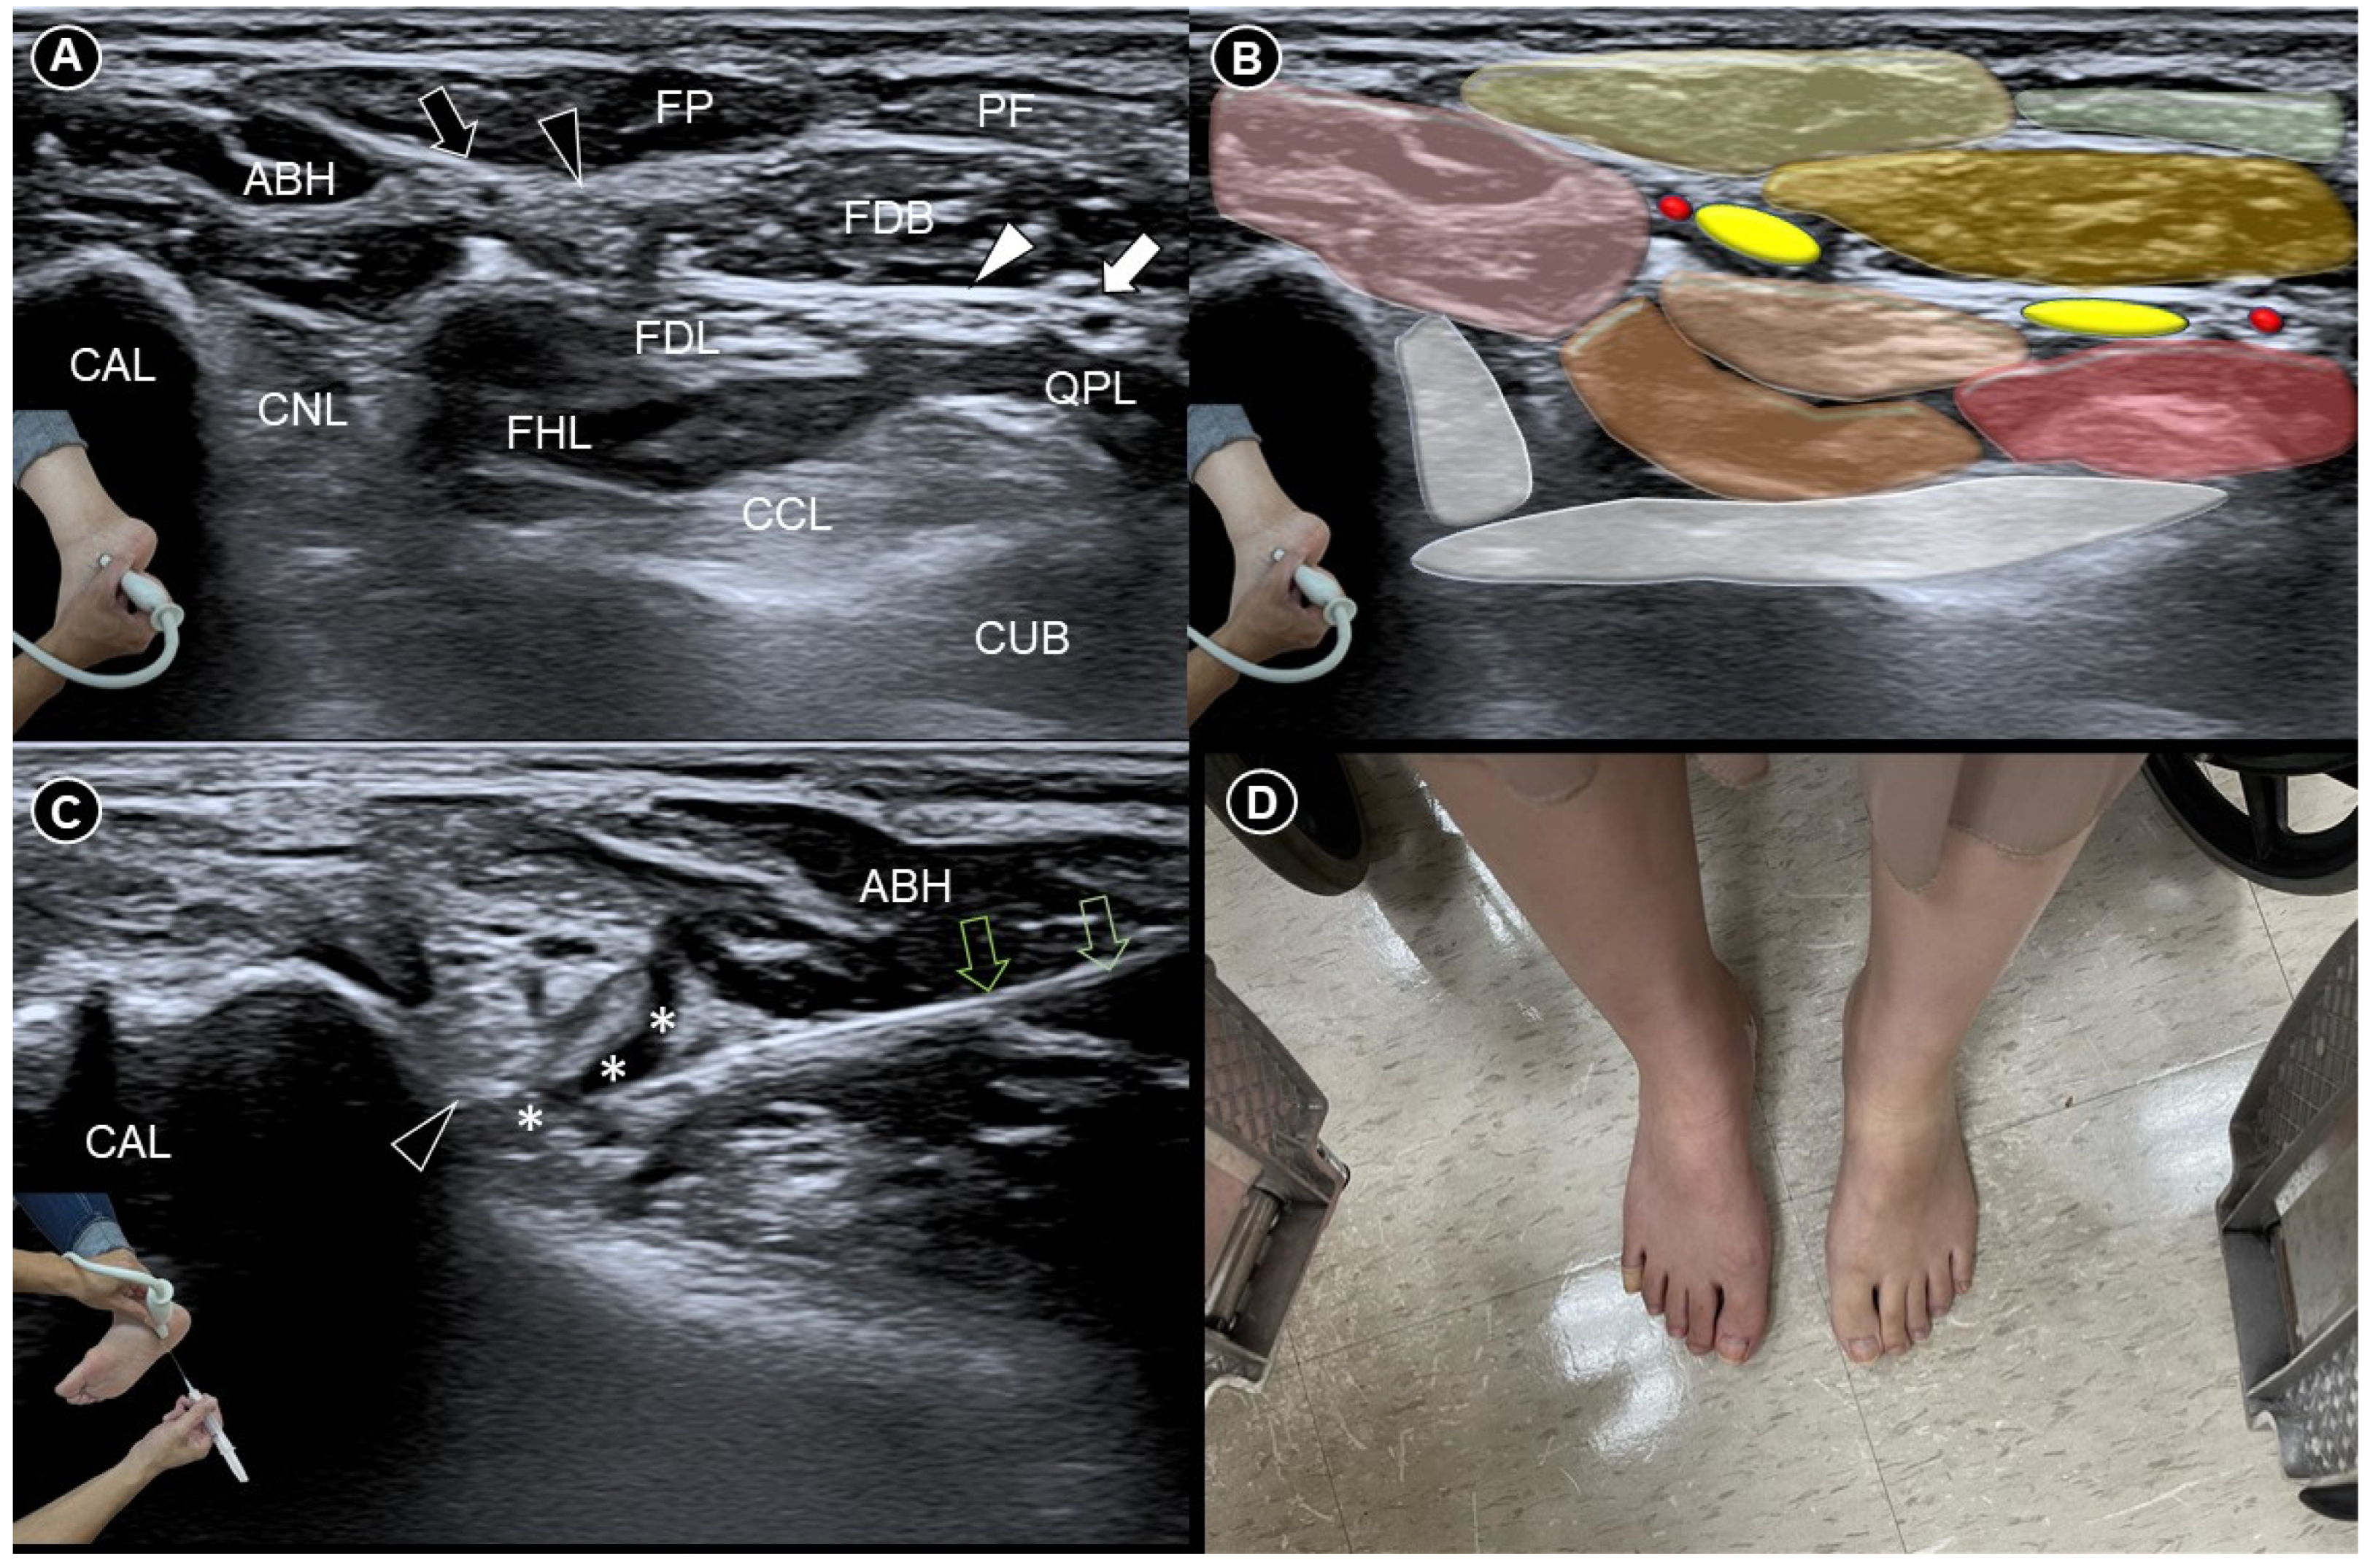

Before the procedure, she experienced pain reproduction when the transducer was placed in the coronal plane over the dome of the medial foot arch. Dynamic flexion and extension of the big and second toes confirmed the pain originating at the Master Knot of Henry (Video S1), where the medial plantar artery, medial plantar nerve, flexor digitorum longus (FDL), and flexor hallucis longus (FHL) tendons intersect (Figure 1A,B). However, no lipoma but a normal fat pad was observed between the flexor digitorum brevis and abductor hallucis brevis muscles. Subsequently, ultrasound-guided hydrodissection using a mixture of 0.5 mL 50% dextrose, 2 mL 1% lidocaine, and 2.5 mL normal saline was performed using an in-plane lateral-to-medial approach (Figure 1C and Video S2). Five minutes post-injection, the injected foot appeared redder and warmer than the contralateral side. She was able to walk barefoot immediately after the procedure (Figure 1D). Following two sessions, her pain significantly reduced, with her visual analogue scale score decreasing from 8 to 5 after the first and to 2 after the second, enabling her to resume normal activities. No complications were observed after each injection.

Figure 1. Ultrasound imaging (A) and schematic drawing (B) of the Master Knot of Henry. Ultrasound-guided medial plantar nerve hydrodissection (C), followed by erythematous skin changes in the injected foot (D). FHL, flexor hallucis longus tendon; FDL, flexor digitorum longus tendon; ABH, abductor hallucis; FDB, flexor digitorum brevis; QPL, quadratus plantae; CAL, calcaneus; CUB, cuboid; FP, fat pad; PF, plantar fascia; CCL, calcaneocuboid ligament; CNL, calcaneonavicular ligament; black arrowhead, medial plantar nerve; black arrow, medial plantar artery; white arrowhead, lateral plantar nerve; white arrow, lateral plantar artery; green void arrows, needle trajectory; asterisks, injectate.